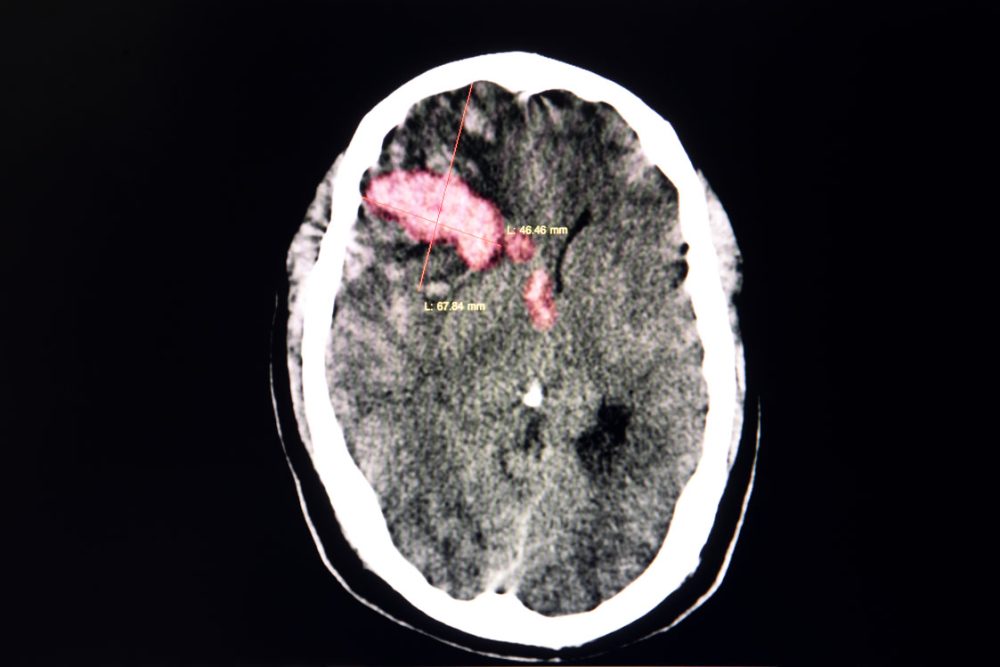

Patients who have suffered an intracerebral hemorrhage (bleeding stroke) who subsequently take statins appear to have a lower risk of having another stroke, especially an ischemic stroke, when compared to similar patients who did not take statins. Researchers reported these findings in Neurology on August 30, 2023.